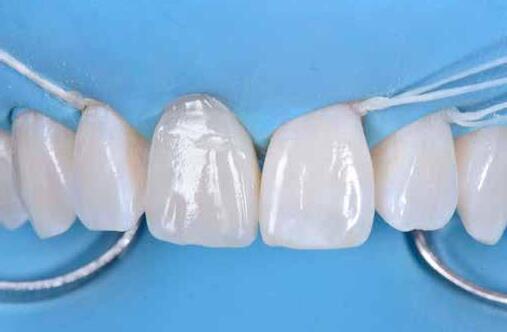

Egy 30 éves, negatív kórtörténettel rendelkező beteg azzal a kéréssel fordult hozzánk, hogy cseréljük ki az UR1 traumája után, 10 évvel korábban készült korábbi kompozit-helyreállítást.

A klinikai vizsgálat során az UR1 reagál a viabilitási tesztre, és az ugyanazon a napon készült röntgenfelvételen nem mutat periapikális elváltozásokat (1. ábra).

Az UR1 elszíneződött, és palatálisabb helyzetben van, mint az ellenoldali központi UL1 (2. ábra)

Az esztétikai elemzés a gingivális zenit aszimmetriáját mutatja az UR1 és az UL1 között. Parodontális szonda segítségével, plexusérzéstelenítés után, az IA

típusú funkcionális hám megváltozott passzív erupcióját igazoljuk Coslet és mtsai. osztályozása szerint (3. ábra)

A lehető legkonzervatívabb helyreállító kezelés elvégzése érdekében a páciensnél, figyelembe véve a megtartott fogelem korát és vitalitását, a tervezés és a diagnosztikai felviaszolás után a közvetlen kompozit-helyreállítás elvégzése mellett döntünk.

A kezelés napján, helyi plexusérzéstelenítést követően, az UR1-et kofferdámmal izoláljuk, kiterjesztve az izolációt az első premolárisokra (4. ábra)

Ezt követően eltávolítjuk a törött kompozt-helyreállítást, és az előkészített fogon rövid ferdére preparálást készítünk, majd az UR1 teljes felületén homokfúvást végzünk 27 μm-es alumínium-oxid porral (5. ábra)

A megváltozott passzív erupció korrigálása érdekében úgy döntöttünk, hogy a fog kiemelkedési profilját a vesztibuláris kidomborodás hangsúlyozásával és az ellenoldali elemmel való szimmetriára törekvéssel újra létrehozzuk. Erre a célra

egy előre megformázott fémmatricát használunk, amelyet két ékkel blokkolunk.

A matrica adaptálása után az adhéziós eljárásokat egy 3 lépéses etch&rinse rendszerrel végezzük. Minden egyes lépést 40 másodperces, UV-fénnyel történő polimerizálás követ (6. ábra)

A vesztibuláris kiemelkedési profilt zománcszínű kompozittal (a TOKUYAMA DENTAL ESTELITE ASTERIA WE termékével) állítjuk helyre (7. ábra).

A diagnosztikai felviaszolás szilikonindexének elkészítése után a palatinális falat zománcszínű kompozittal (a TOKUYAMA DENTAL ESTELITE ASTERIA WE termékével) helyreállítjuk (8. ábra)

Ezt követően helyreállítjuk a dentin anatómiáját a mamelonok reprodukálásával egy átlátszatlan dentinszínű kompozittal (a TOKUYAMA DENTAL ESTELITE SIGMA QUICK OA2 termékével); ez a szín alapvető fontosságú lesz a diszkromatikus elem színének korrigálásához is (9. ábra) Világoskék és fehér hatású árnyalatokat (a TOKUYAMA

DENTAL ESTELITE COLOR termékét) alkalmazunk az opá-

losság emulálásához az incizális területen (10. ábra)

A rétegezést egy zománcszín (a TOKUYAMA DENTAL ESTELITE ASTERIA WE terméke) használatával végezzük a vesztibulárisban, egyszeri hozzáadással. A vesztibuláris felületet háromdimenziós térfogatban modellezzük és vezéreljük annak érdekében, hogy a lehető legkevesebb végső kiigazítás legyen. Ezután 20 másodpercig polimerizáljuk, majd 40 másodpercig polimerizáljuk vesztibulárisan és palatinálisan, miután bevontuk őket gliceringéllel a kompozit hibrid rétegének elkerülése érdekében (11. ábra).

A finírozási és polírozási eljárásokat úgy végezzük, hogy megpróbáljuk emulálni az UL1 átmenő vonalait (12–13. ábra)

A pácienst 21 nap (14–15. ábrák) és 12 hónap (16. ábra) után ismét ellenőrizzük, hogy értékeljük az esztétikai eredményt a forma és a szín tekintetében.